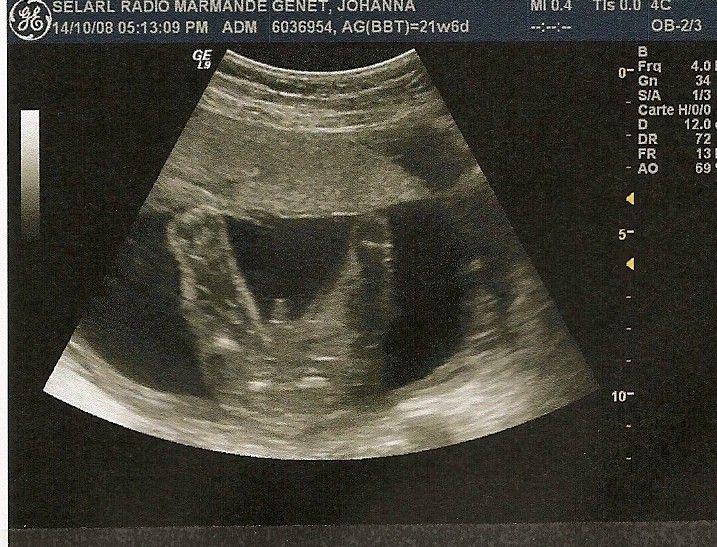

Par LUCIOL : le 04/12/08 à 16:44:46

| Dire merci | Dark, la solution prend une photo de l'échographie avec ton apn. C est moin beau qu avec le scanner, mais bon..c est mieux que rien, moi c est comme ca que j ai fait :![]() |

Par candia : le 06/12/08 à 11:06:21

| Dire merci | ![]() coucou les filles voici mon petit garçon déja trés coquin qui montre ses petites fesses ça y est je suis en arrêt car beaucoup de contractions mais encore beaucoup de boulot avec mes chevaux car la saison d monte arrive a grand pas ainsi que celle des courses et tout ça en plein dans mon terme j'angoisse un peu et ne voudrai pas accoucher dans un van ![]() il me tarde ma dernière echo pour savoir si tout va bien et si mon placenta est remonté sinon ça sera césarienne ![]() en tout cas tout a fait d'accord avec toi luciol moi aussi je me sens grosse je suis déja à 10 kg avec 6 pris le mois dernier et il me reste 2 mois et demien fait g tout pris dans le ventre et le pti gars et déja bien dodu |

lee: merci ![]() candia : marrante la "photo" lol moi aussi 10kg mais seulement 2 pris le mois dernier , et les mois 4 et 4 et avant rien . et jai aussi pris tout le bide . mais bon comme je suis tres grande ca va ![]() |